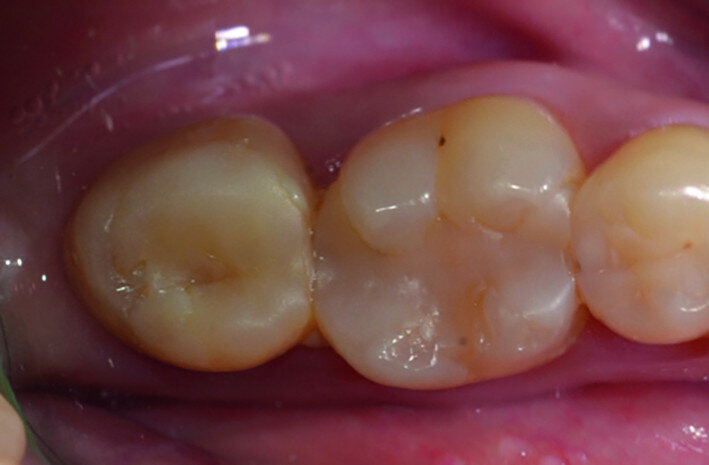

Fig. 2: Pre-op facial view.

A 47-year-old male patient in a good medical condition and a non-smoker was referred to our dental practice for endodontic retreatment of the right maxillary second molar. The dental history revealed that the tooth had been endodontically treated three months before because of acute pulpitis. After the treatment, the patient complained of pain on chewing. Antibiotics and a non-steroidal anti-inflammatory drug were prescribed, but the pain remained. After a month, a sinus tract appeared. The tooth was retreated in another practice without success. The clinical inspection revealed the presence of a sinus tract near the apical region of tooth #17. The tooth had been prepared for a full crown, but was without even a temporary crown, and the access cavity had been closed with temporary filling material. Cracks were evident on the buccal and mesial surfaces. Periodontal probing showed a deep pocket (> 12 mm) on the distal aspect of the root trunk (Figs. 1 & 2). The periapical radiograph showed a radiolucency between the roots of the second and third molars. The radiographic appearance of the endodontic treatment was good, without clear evidence of periapical radiolucencies (Fig. 3). A perforation of the pulp chamber floor was suspected. A CBCT scan was performed (Figs. 4–7), and it confirmed the suspicion of perforation, along with the presence of a large periradicular radiolucency and an unfavourable root shape.